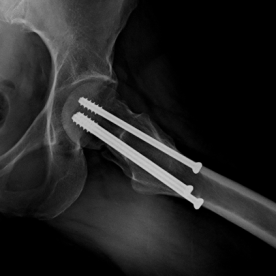

Röntgenbilder